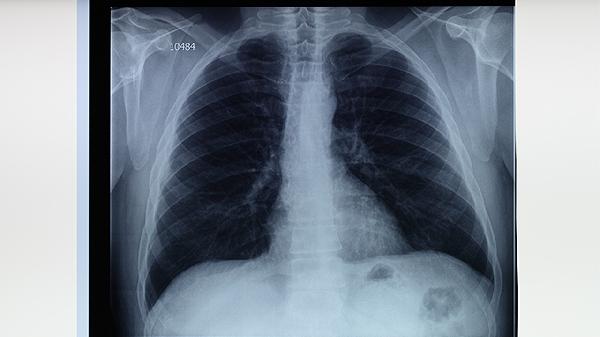

规范抗结核治疗2-3个月后,若患者仍有持续咳嗽超过2周、午后低热、夜间盗汗、体重下降等症状,需警惕耐药可能。胸部影像学显示病灶吸收不佳或出现新病灶,痰涂片持续阳性也提示耐药。此时应重新评估治疗方案,及时进行耐药检测。